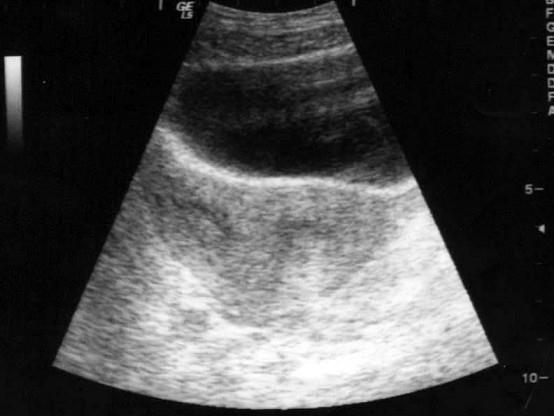

下图诊断最可能是 ( )A、纵隔子宫B、以上均是C、残角子宫D、双角子宫E、双子宫

选项 A、纵隔子宫 B、以上均是 C、残角子宫 D、双角子宫 E、双子宫

答案 A